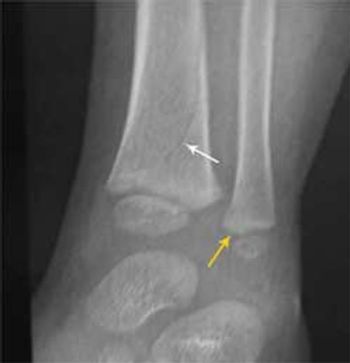

A 16-month-old toddler was brought to the emergency department after he and the sibling who was carrying him fell down a flight of stairs. The child had not been able to bear weight on his left ankle since the fall and resisted his mother's efforts to put on his shoe. Prior medical records showed no history of broken bones or evidence of past abuse or questionable injuries.